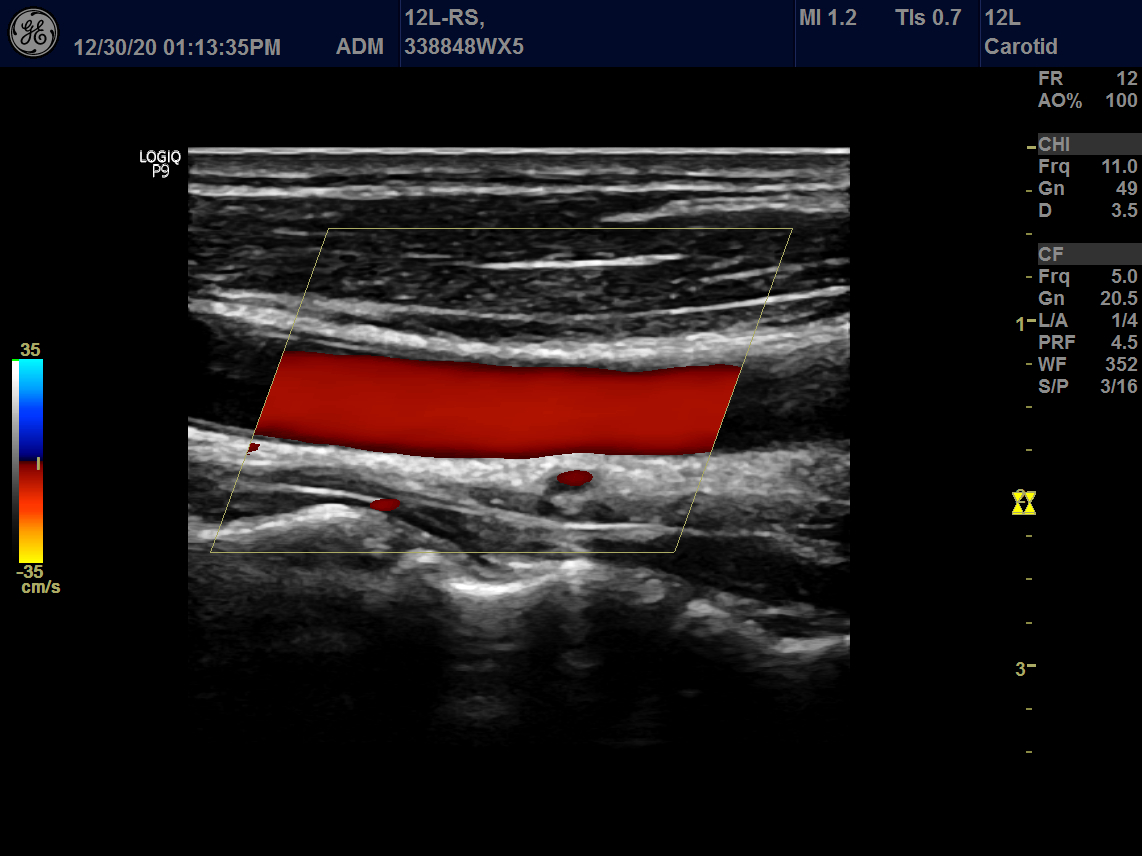

Intended use

Vascular, Small Parts and Musculoskeletal

GE 12L-RS Vascular Linear

Frequency Range: 13 – 4 MHz

GE 12L-RS Vascular Linear for Vascular, Small Parts and Musculoskeletal